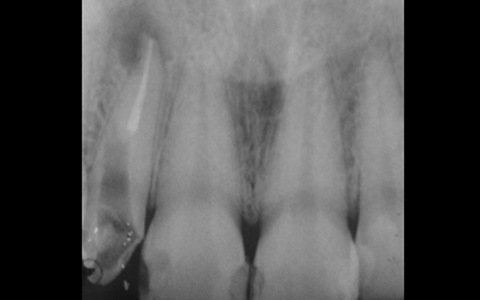

さらに再根管治療をしている歯のCTを撮影すると、歯根が破折していないにも関わらず、CTでは歯根が破折しているように見えることがあり、実は私達が見ているレントゲン(CTも含めて)は、その画像だけでは正しく診断できません。

通常のレントゲンは平面による撮影のため情報量少なく正確な診断が難しいですが、歯科用CTは三次元の立体的な画像で確認することができるため、神経の位置や根管内もしっかりと確認できます。

精密な治療をご提供するために、歯科用CTによる正確な画像診断を行うことがあります。

どこまで根管治療が行われているのかをレントゲン撮影により確認するだけではなく、細菌検査による無菌化の確認も行っています。これにより治療の成功率が格段に向上します。